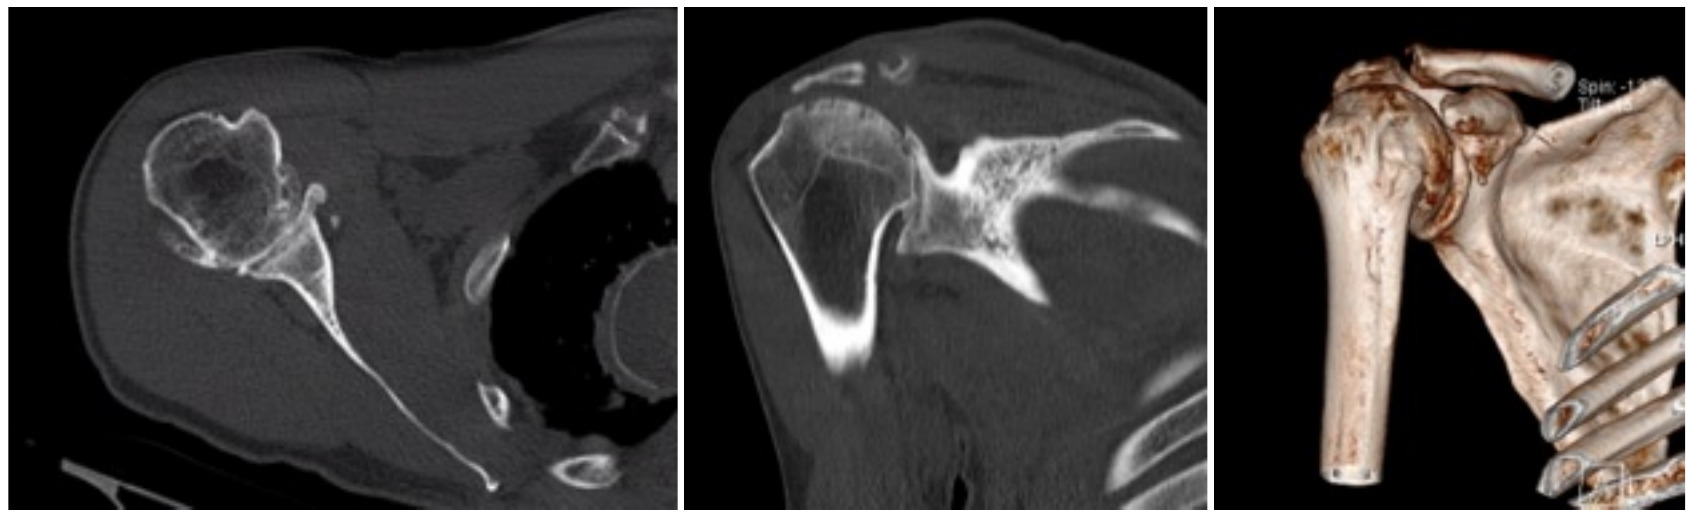

Case one is a 58-year-old male who is an avid golfer with long standing right shoulder pain. Surgical history includes previous Bristow procedure 30 years prior. Current Subjective Shoulder Value (SSV) is 30% and pain is 8/10 at baseline. Active range of motion was 110° of forward flexion, -10° of external rotation and interna rotation to the lateral buttock. Radiographs (Figure 1) and computed topography (CT) scan (Figure 2) show retained implants with loss of joint space, glenoid retroversion, and significant posterior humeral head subluxation. The patient had failed conservative management and was indicated for arthroplasty. Due to significant posterior bone loss and retroversion, an augmented anatomic component was selected for this patient. Radiographs at one year show a well seated glenoid component with restoration of the joint line and a centered humeral head (Figure 3). At five years, SSV had improved to 95% with excellent clinical motion (Figure 4).